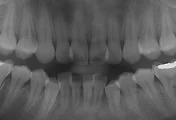

저의 사진을 보시죠.

치료전

치료후

7년후 현재 입니다.

이제 아시겠죠? 교정치료결과는 조금 돌아가는 겁니다.^^*